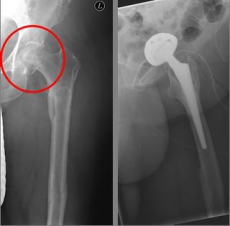

In older age and with stronger displacement of the fracture can be done by a duo-head prosthesis. Here only the femoral head is replaced, the hip socket is preserved. In case of simultaneous hip arthrosis, a total endoprosthesis (hip replacement) with replacement of the acetabular cup can be used.

Picture: This picture shows the treatment of a severely displaced fracture with a so-called duo head prosthesis. The acetabulum was left here.

Picture: In this case, there was already a wear of the hip joint and the affected patient was relatively young, so that a cement-free total endoprosthesis (TEP) of the hip was selected for the treatment of the femoral neck fracture. Here, in addition to the femoral head, the acetabular cup was replaced by an implant.